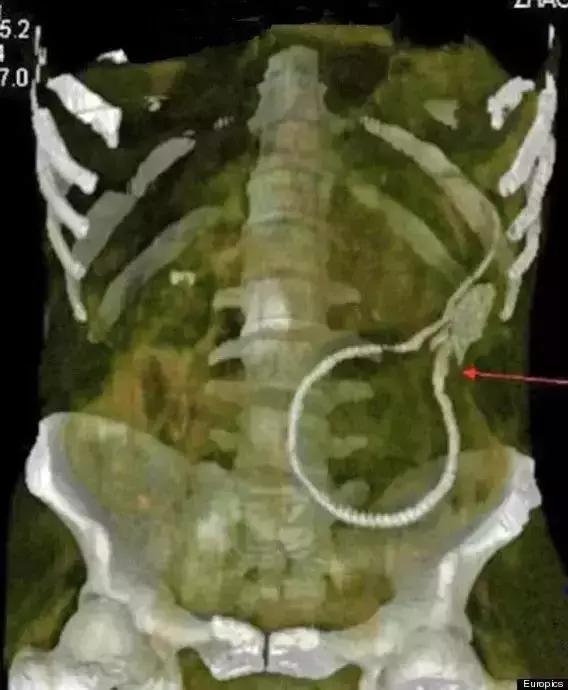

▲鳝鱼(这,这我不好发表看法)

最后,是“看图识物”环节,请大家辨认下面三张图中的物体,欢迎在留言区发表你的看法哦。